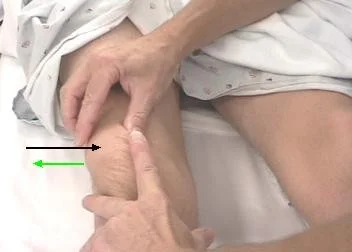

Effusion Tests

-

Large effusion is easy to see

-

Assessment of effusion severity:

-

Look at normal depression medial to patella

-

Minimal effusion: If depression present, “milking” test may demonstrate fluid

-

Mild effusion: If obliterated, fluid can be pushed away but reappears as hand is removed

-

Moderate effusion: If obliterated and fluid cannot be pushed away by hand

-

Moderate/severe effusion: Positive patellar tap (Balloting)